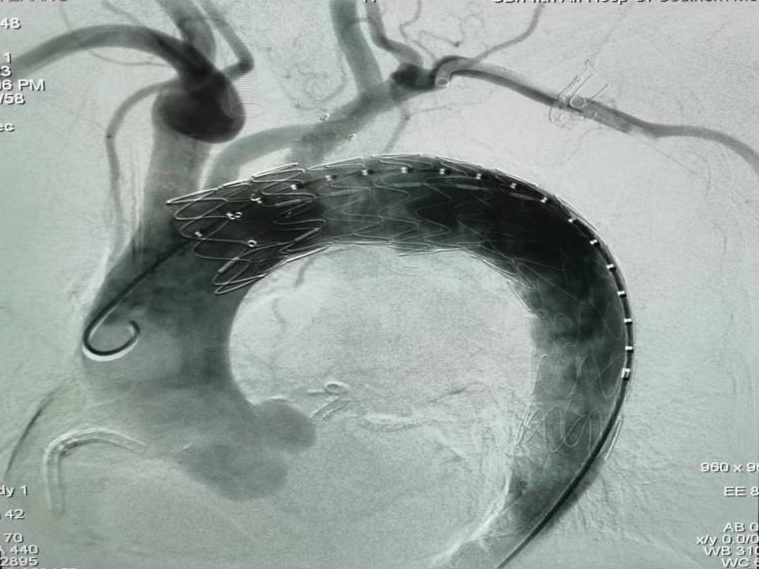

介入血管外科:“原位开窗术”成功救治B型主动脉病变患者

发布时间:2023-08-28 11:03:51

近日,南方医科大学第五附属医院介入血管外科团队独立完成了一例胸主动脉夹层覆膜支架腔内隔绝+原位开窗手术。整个团队经过2小时的努力,顺利完成了手术,患者安全返回病房。 75岁的患者在南方医科大学第五附属医院就诊期间,主动脉CTA提示:主动脉弓部...